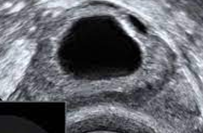

Unauffällige oviarielle Reserve, AFC 8

Reduzierte ovarielle Reserve, AFC 2

AFC erhöht bei PCOS, ACF > 15